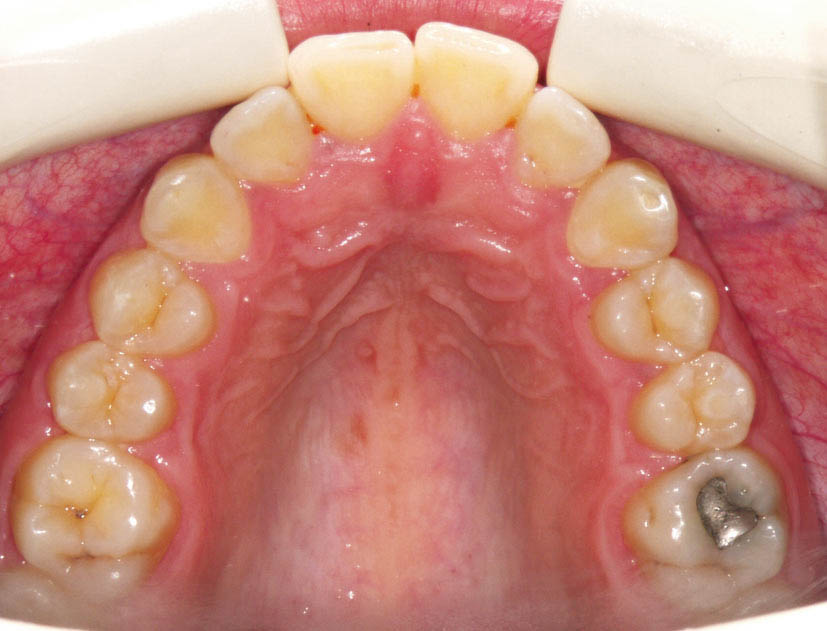

خیلی از مواقع بیمار دندانهای مرتبی در فک بالا دارد و اگر به تنهایی به آن نگاه کنید درمان غیرکشیدنی برای شما تداعی میشود (شکل 93-2) در حالیکه شاید اورجت زیادی داشته باشد و مجبور به کشیدن باشید (شکل 94-2 و 90-2)

شکل 93-2: مرتب بودن دندانهای قوس بالا